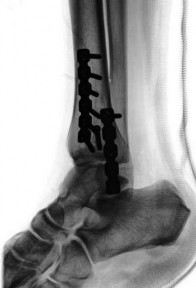

When treating a proximal tibia fracture, the surgeon decides to (1) use blocking screws in the proximal fragment, and (2) pick the intramedullary nail based on the location of the Herzog curve. Which of the following combinations will best prevent the classic deformity associated with this fracture? ](http://www.orthobullets.com/trauma/1062/proximal-third-tibia-fracture)